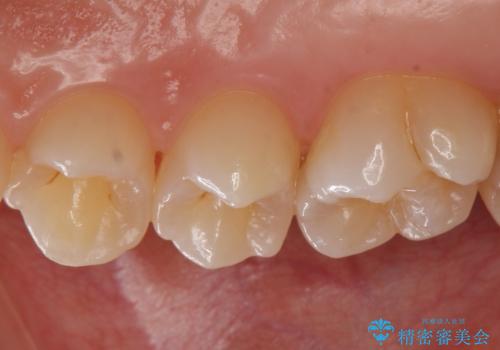

歯と歯の間の虫歯 セラミックインレーでの治療

歯と歯の間に虫歯があったためセラミックインレーで治療をしていきました。

歯と歯の間は虫歯の好発部位となっています。

今後の虫歯リスクを抑えるためにも適合の良い補綴物を装着することは有効です。